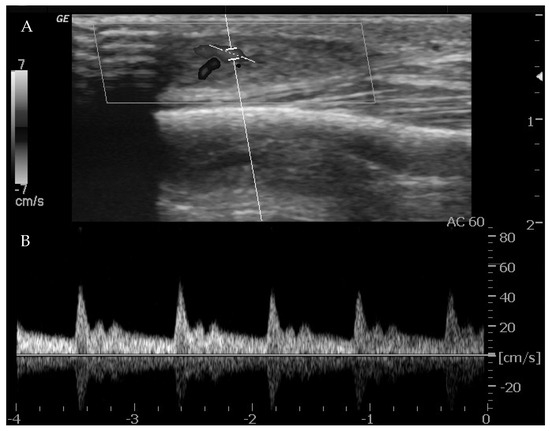

Ultrasounds can provide indications of the exact type of lesion and can help to distinguish it from other lesions. It is also possible to gather information on the morphology (size, anatomical location and depth), number and compressibility (hard, non-compressible lesions are always suspicious for a malignant nature) [44]. It can also discriminate high-flow from low-flow anomalies and frequently offers a specific diagnosis when there are characteristic features of VMs (4, 10, 15, 18, 20). The presence of arterial flow is suggestive of high-flow lesions such as hemangiomas, other vascular tumors and high-flow VMs (Figure 1).

When arterial flow is recognized on Doppler US, further considerations can be made. High vessel denseness and high Peak Systolic Velocity (PSV) can be recognized. More information can be gained by calculation of resistive index: the arteries inside high-flow VA show low-resistance flow, with low values of resistive index (RI).

However, it must be considered that one or a few areas of arterial flow could also be observed within low-flow VM, e.g., venous and lymphatic malformations which frequently infiltrate around normal structures, and a few arterial vessels might be seen passing through them. Also, lymphatic malformations can show areas of arterial flow inside the septa/walls of their cystic component. These foci of arterial flow inside low-flow lesions show high RI values, in contrast to arteries within high-flow lesions [43].

Figure 1. Ultrasound imaging with power Doppler on the thigh. (A). A well-defined, solid, ovoid lesion is seen in the subcutaneous plane, without calcification or cystic changes. (B). Significant flow is noted on color Doppler with an artery entering and exiting the lesion.